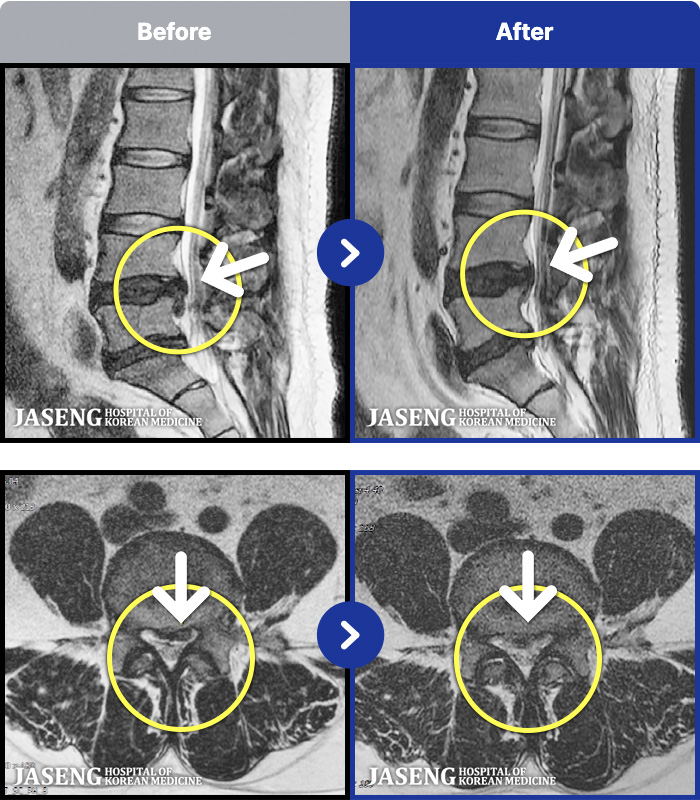

1,301 MRI ũ ʸ Ȯϼ.